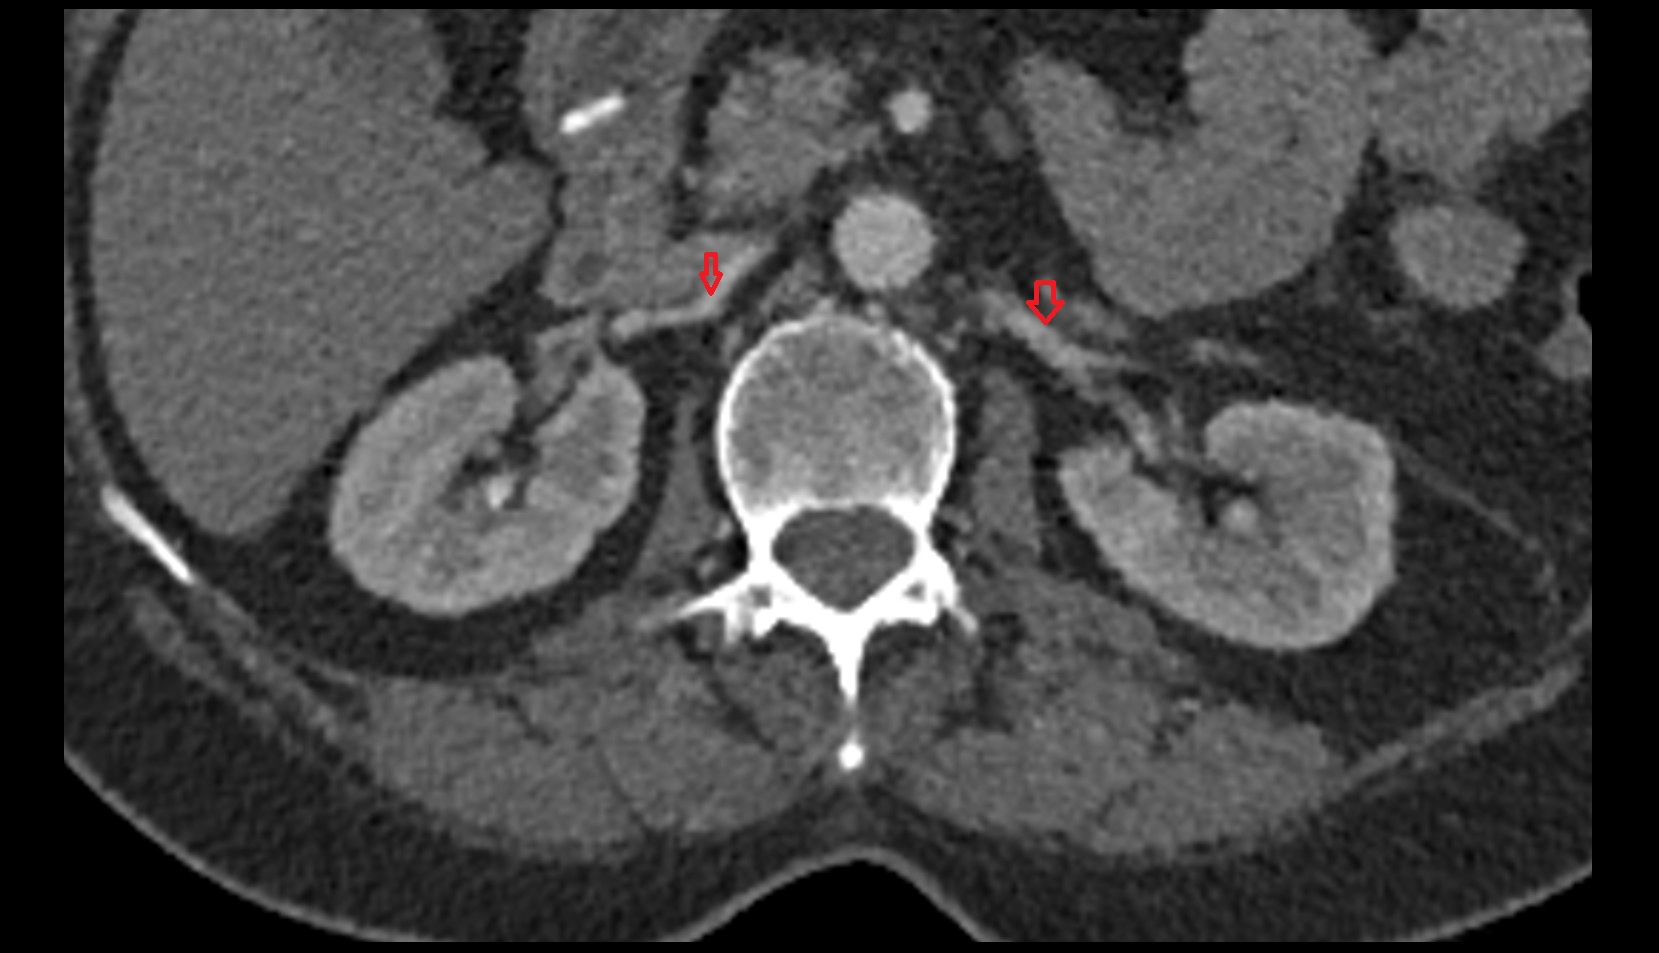

- kidneys

- Right kidney

- Left kidney

- Kidney cortex (Renal cortex)

- Renal medulla

- Renal pyramids

- Ureters

- Renal artery

- Renal vein

- Left renal vein

- Right renal vein

- Left renal artery

- Right renal artery